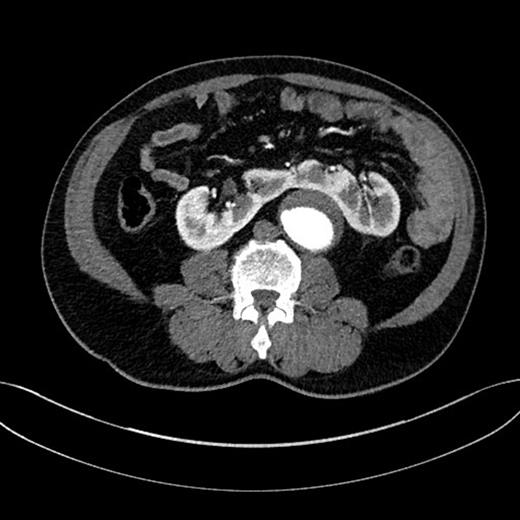

Using a transperitoneal approach, we identified a juxtarenal AAA and a HSK with both renal pelvises located medially. The renal isthmus closely lied over the aneurysm, and there was a small vein draining blood from the renal isthmus to the left renal vein, but no accessory artery supplying the renal isthmus was found (Fig. 2). Both ureters were identified and preserved. The left renal artery was identified and dissected free from the proximal neck of the aneurysm. Provisional clamping of the left renal artery resulted in ischaemia of the left kidney and the renal isthmus, indicating that the arterial blood supply of the renal isthmus was from the left renal artery. Considering the minimal gap between the aneurysm and the renal isthmus, we had concerns over controlling retrograde lumbar bleeding when the aneurysm is open; therefore, we decided to divide the renal isthmus in order to facilitate exposure of the aneurysm. The left renal vein was preserved, and the vein draining the renal isthmus was divided and ligated. Careful division of the renal isthmus over the aneurysm was carried out, and homeostasis was achieved.

(a) HSK (the isthmus), (b) the distal segment of aneurysm close to the iliac bifurcation, (c) the aneurysm neck, (d) the left renal vein and (e) the left ureter.